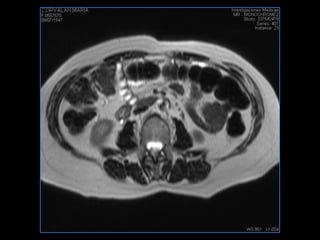

PROTOCOLO abdomen COR T2, AXIAL supresion grasa AX T1 +SAG T2  CON   GADOLINIO :  COR T1+AX T1(DIN) SAT: NO  FASE: RL THK: 6MM  COIL:  GAP: (FACTOR 1.4) 2MM FOV: 40 CM NEX:2 SINCRONIZACION RESPIRATORIA EN 3 O 4 CICLOS ALE